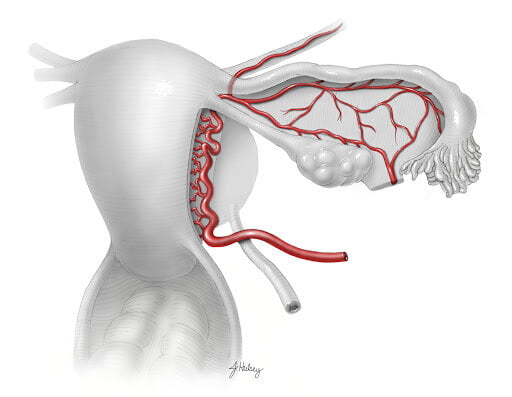

Al llegar al cuello del útero a cada lado, las arterias uterinas desprenden una rama ascendente, que discurre en forma superior a lo largo del útero, y una rama descendente que discurre en forma inferior hacia la vagina.

A nivel de la unión cervico-uterina, la arteria uterina se divide en una rama ascendente y otra descendente.

Pasa de manera superior y tortuosa a lo largo de la pared lateral del cuerpo del útero hacia la trompa uterina. A lo largo de su curso, la rama ascendente desprende múltiples pequeñas ramas que entran en la pared lateral del útero, y se ramifica en el miometrio del útero en las arterias helicina, arcada, radial, espiral y basal.

La rama ascendente continúa en forma superior hasta llegar a la trompa uterina en la región del hilio ovárico, donde se divide en ramas ováricas y tubáricas.

Estas ramas se anastomosan con las ramas ováricas y tubáricas de la arteria ovárica. En resumen, la rama ascendente abastece el margen lateral del útero, la porción media del ovario y el tubo uterino.

Rama descendente

Pasa inferiormente hacia la vagina. Esta rama vaginal se anastomosa con ramas de la arteria vaginal formando arterias longitudinales medianas y arterias ácigos de la vagina, que descienden a lo largo de la pared anterior y posterior de la vagina.

A lo largo de su curso, la rama descendente irriga el cuello uterino y la vagina.